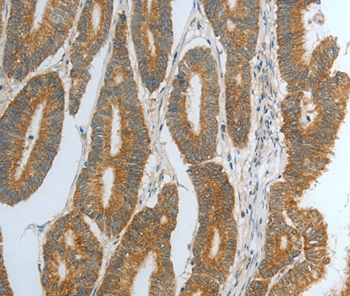

图片:

Immunohistochemical analysis of paraffin-embedded Human cervical cancer tissue using #35859 at dilution 1/15.

,

Immunohistochemical analysis of paraffin-embedded Human colon cancer tissue using #35859 at dilution 1/15.